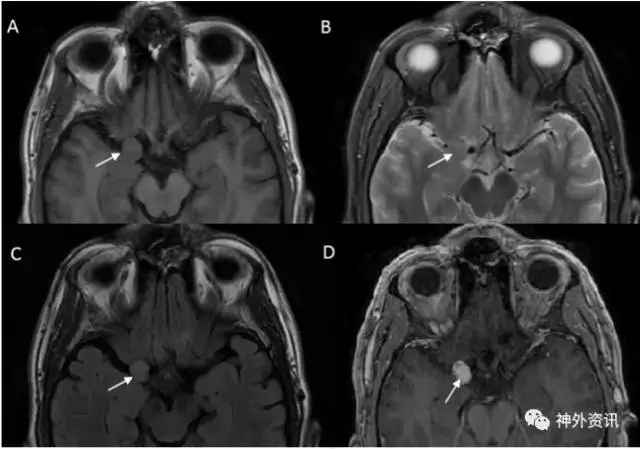

图1. MRI轴位成像显示右侧前床突上方一起源于硬脑膜的占位病变(白色箭头)。A图为T1加权相;B图为T2加权相;C图为T2-FLAIR相;D图为T1加权相增强。

36岁男性患者。因外伤后行影像学检查,意外发现右侧中颅窝占位病变,无临床症状。术前MRI检查显示,右侧前床突一起源于硬脑膜的肿物,T1加权呈低信号,T2加权呈等信号,增强扫描均匀强化,考虑为脑膜瘤。经右侧翼点入路全切除病灶,无术后并发症。术后病理学检查,见病变为扩张、硬化的血管团,间质无神经组织,血管内有血栓形成,符合海绵状血管瘤。